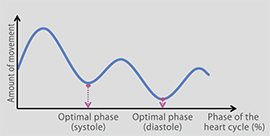

В ходе подготовки системы к сканированию автоматически настраиваются условия оптимального сканирования на основании результатов анализа ритма сердечных сокращений. Все операции просты настолько, что даже число данных в полученных сегментах определяется системой автоматически, исходя из частоты сердечных сокращений во время сканирования.Автоматический контроль дозы

В ходе подготовки системы к сканированию автоматически настраиваются условия оптимального сканирования на основании результатов анализа ритма сердечных сокращений. Все операции просты настолько, что даже число данных в полученных сегментах определяется системой автоматически, исходя из частоты сердечных сокращений во время сканирования.

Функция правки по электрокардиограммеВ случае аритмии или существенных колебаний ЧСС электрокардиографическая волна и реконструированная фаза могут быть автоматически подвергнуты правке.